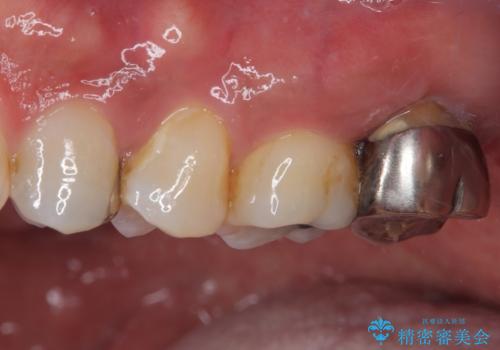

- 奥歯の周りの歯肉が腫れており、噛む度に痛みを感じるとのことで来院された患者様です。

ご自身の感覚として、抜歯は免れないと判断されており、インプラント治療を希望されていました。

レントゲンや診察を行ったところ、抜歯となる可能性はありましたが、まずは銀歯を外した上で根管治療を行うことが可能であるか判断することが先決であるとご説明し、根管治療とインプラント治療の双方をご案内し、治療を開始することとしました。

骨の透過像が非常に大きく、根管も大きく削られていたため、歯根破折による抜歯の可能性がありましたが、根管治療可能な状態でした。